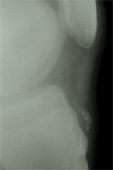

Radiographie

du genou douloureux de face et de profil

Ce bilan radiologique est le plus souvent normal.

La radiographie a donné

lieu à une classification qui n’est pas utile pour la prise

en charge thérapeutique, classification

d'Ehrenborg (1962).

Les images radiographiques peuvent être normales, mais après

6 à 8 mois d’évolution, on peut retrouver un aspect

ossiculaire (fragmenté) à la base du tendon rotulien dans

30% des cas.

Ces fragments fusionnent progressivement avec le noyau d’ossification

pour provoquer un aspect d’hypertrophie de la TTA, très

souvent seule séquelle esthétique de la maladie.

Type 1 aspect radiographique osseux normal, simple oedème des parties molles.

Type 2 avec aspect irrégulier du noyau apophysaire et micro-fragments.

Type 3 avec une image d’ossification en avant du relief de la tubérosité tibiale antérieure.

Type 4 avec fragment ostéo-cartilagnieux intra-tendineux.